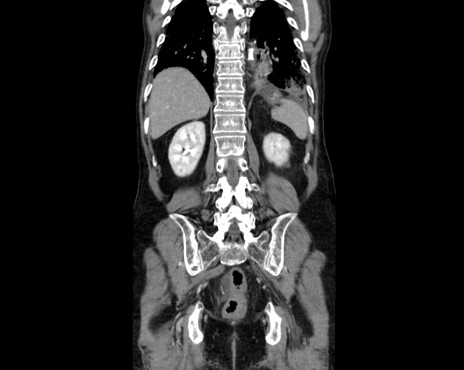

症例26(冠状断像)

【症例】80歳代男性

【主訴】嘔吐

【現病歴】昨晩2回嘔吐あり、今朝になっても嘔吐あり。来院。

【既往歴】胃潰瘍

【身体所見】意識清明、BT 37.6℃、BP 166/95mmHg、HR 100bpm、SpO2 97%、腹部:平坦・軟、腸蠕動音聴取良好、圧痛なし。

【データ】WBC 21900、CRP 1.4